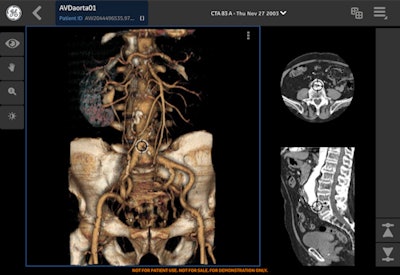

The Centricity Cloud Advanced Visualization radiology app is being promoted by GE Healthcare at ECR 2016.Four new applications include an advanced visualization app for managing image postprocessing and allowing radiologists and clinicians to view advanced 3D images anytime, anywhere. There is also a virtual meeting app to help multidisciplinary teams in their collaborative care planning and reducing preparation time for such meetings by up to 20%. The company is also presenting a case exchange app allowing affiliated and nonaffiliated users to share images and reports and to confer quickly on patient cases and treatment plans. Finally, there is an image access portal for distributing longitudinal patient imaging data, offering potential improvements in turnaround times for patient reports.